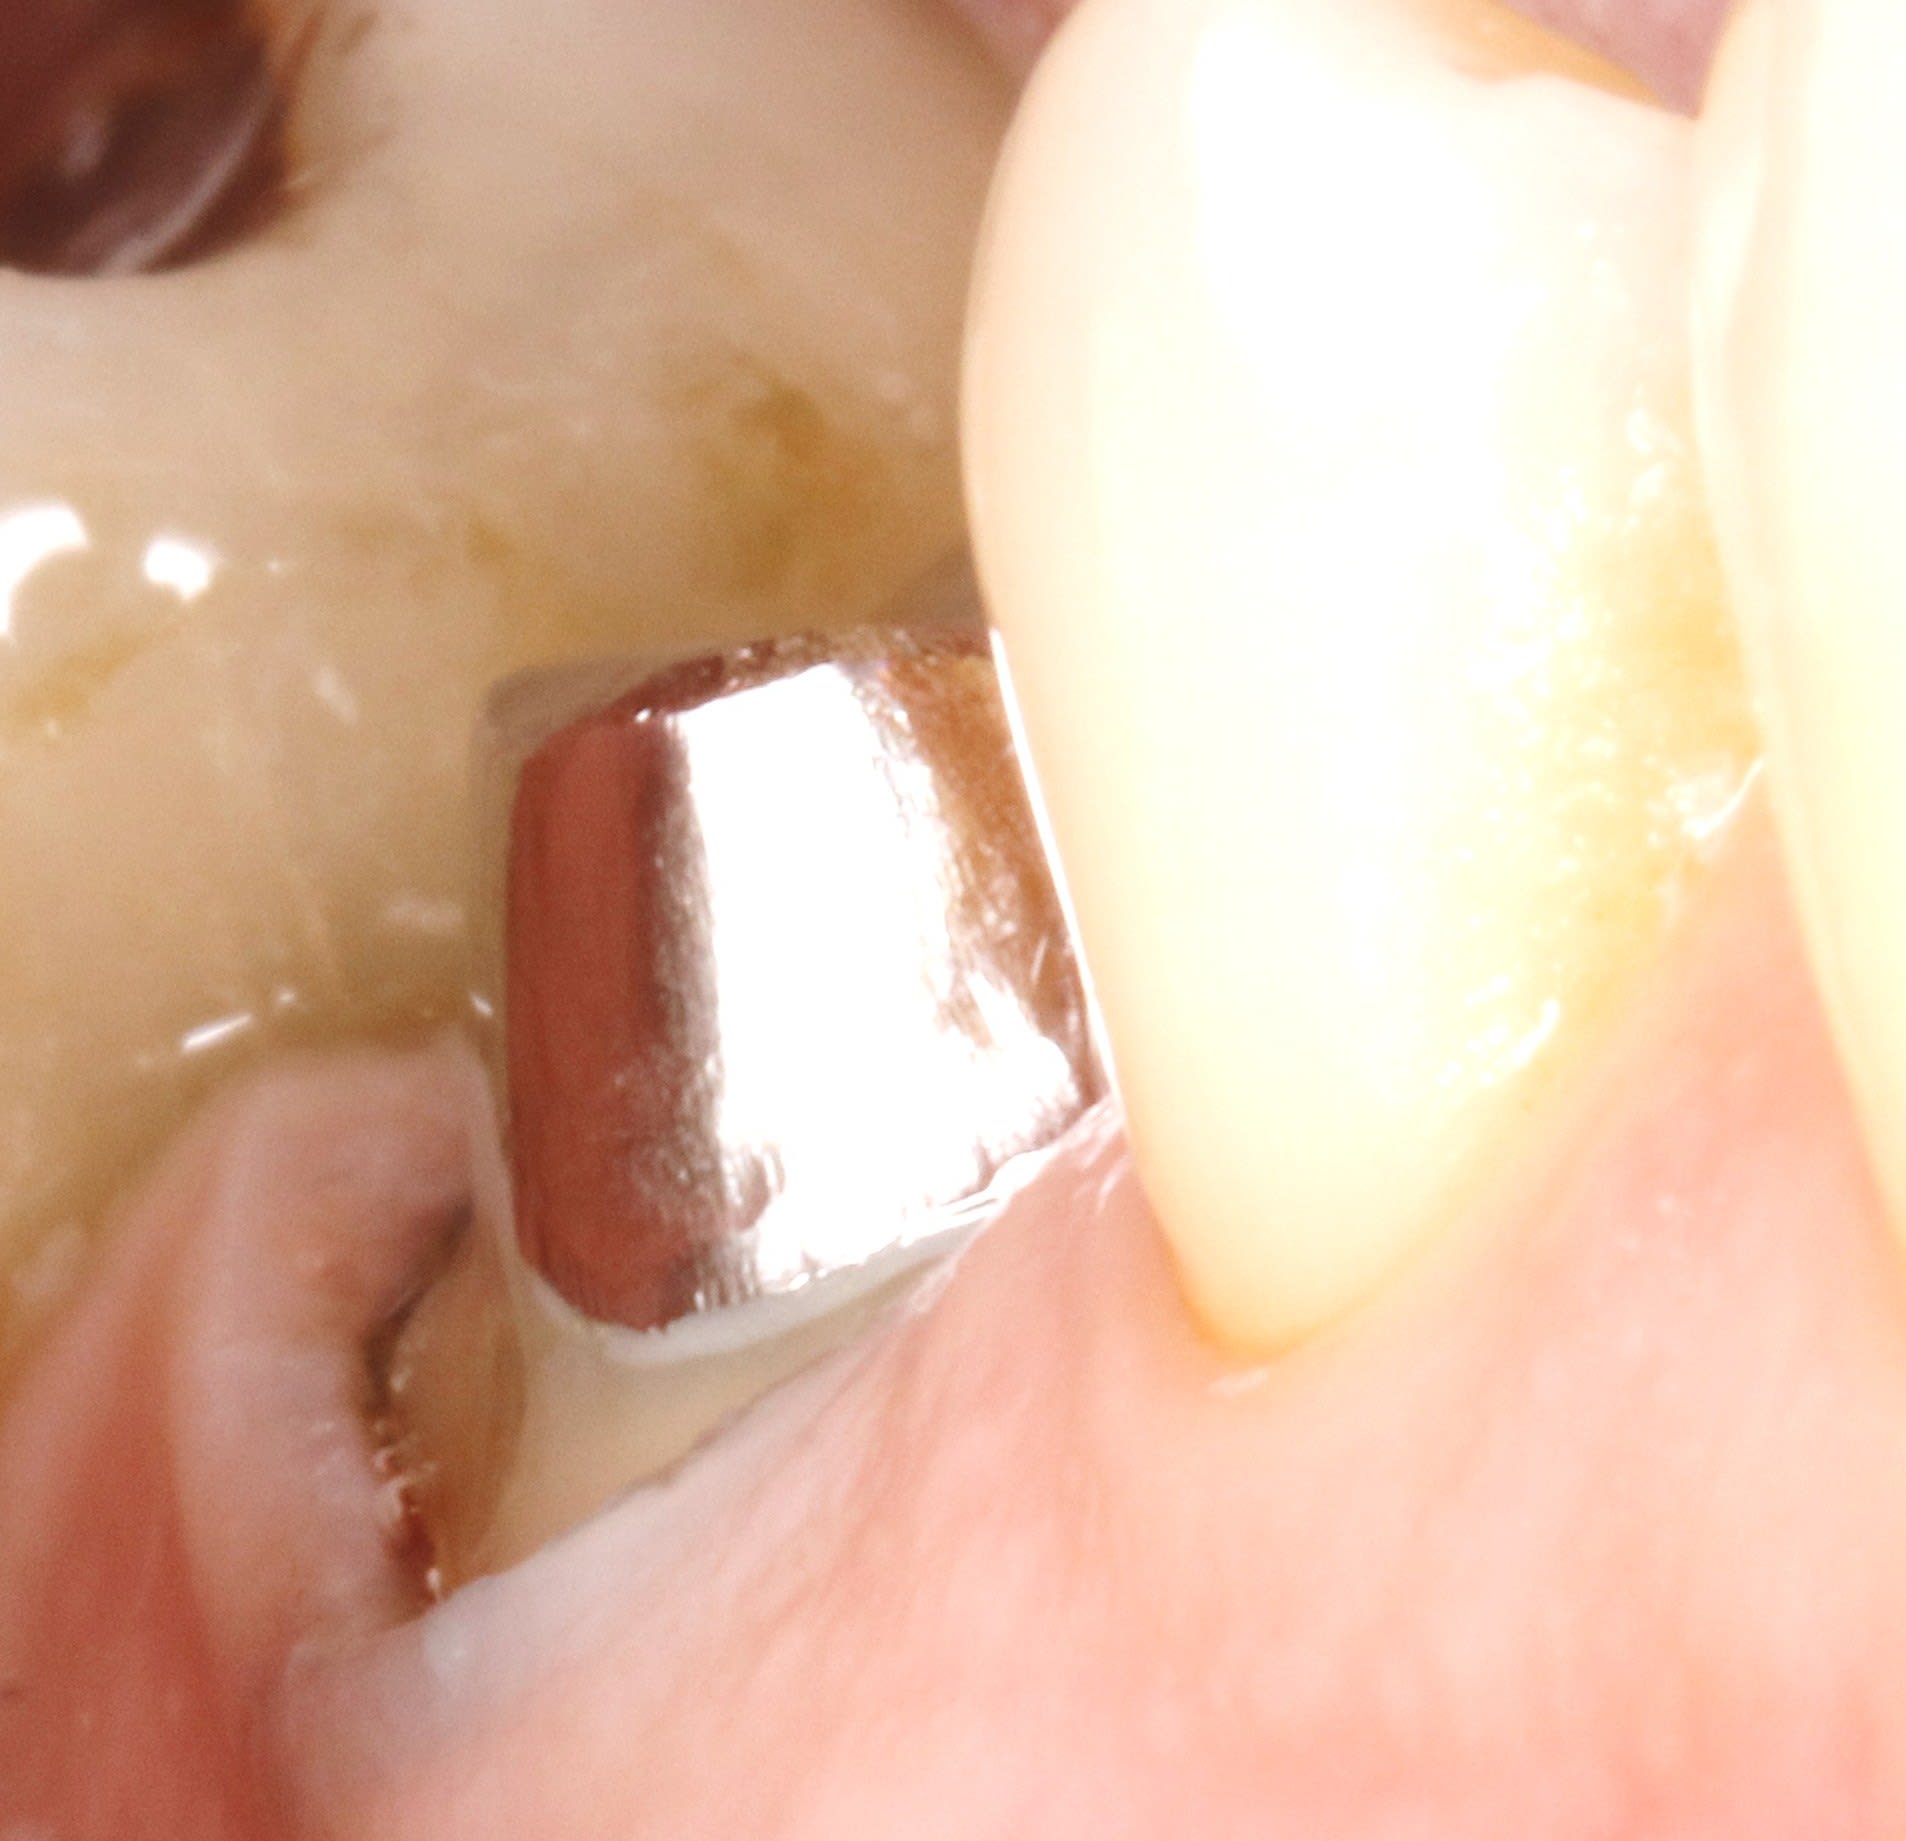

on peut mettre 1 fil , et meme se servir du chausse pied , ça ne saignera pas , ç est du beurre .

et on reprecise les limites à la grain fin .

mg 1521 slgrg3 - Eugenol